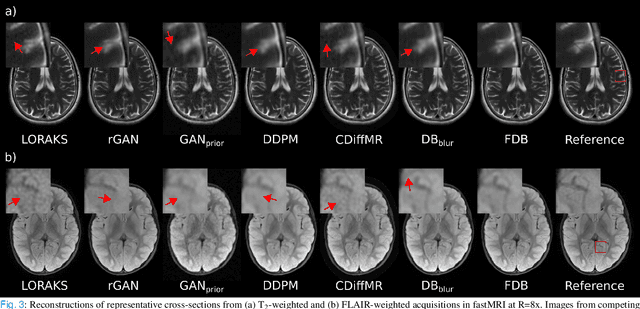

Abstract:Recent years have witnessed a surge in deep generative models for accelerated MRI reconstruction. Diffusion priors in particular have gained traction with their superior representational fidelity and diversity. Instead of the target transformation from undersampled to fully-sampled data, common diffusion priors are trained to learn a multi-step transformation from Gaussian noise onto fully-sampled data. During inference, data-fidelity projections are injected in between reverse diffusion steps to reach a compromise solution within the span of both the diffusion prior and the imaging operator. Unfortunately, suboptimal solutions can arise as the normality assumption of the diffusion prior causes divergence between learned and target transformations. To address this limitation, here we introduce the first diffusion bridge for accelerated MRI reconstruction. The proposed Fourier-constrained diffusion bridge (FDB) leverages a generalized process to transform between undersampled and fully-sampled data via random noise addition and random frequency removal as degradation operators. Unlike common diffusion priors that use an asymptotic endpoint based on Gaussian noise, FDB captures a transformation between finite endpoints where the initial endpoint is based on moderate degradation of fully-sampled data. Demonstrations on brain MRI indicate that FDB outperforms state-of-the-art reconstruction methods including conventional diffusion priors.